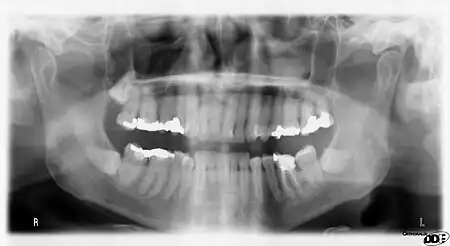

Panoramic x-ray radiography of the teeth of a 64-year-old male. Dental work performed mostly in UK/Europe in last half of 20th Century